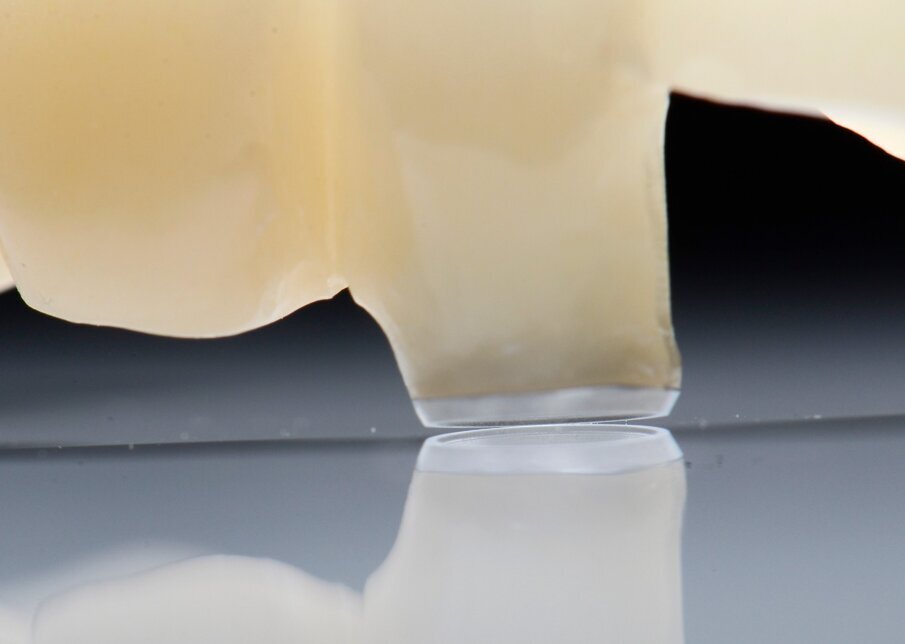

Alloggiamo la dima protesica (Fig. 33), e blocchiamo i transfert con della resina trasparente (tecnica DIL) (Figg. 34, 35). In questo modo possiamo far riposare il paziente in studio dopo appena 35 minuti dall’inizio dell’intervento. La dima protesica, infatti (Fig. 36) con i transfert inseriti viene completata con l’unione degli analoghi ai transfert (Fig. 37). L’insieme così composto viene riadattato sul modello master digitale iniziale (Figg. 38-40) sul quale era stata costruita sia la dima chirurgica che la dima protesica come anche il provvisorio. Gli analoghi vengono bloccati sul modello con resina trasparente (Figg. 41-43). Alloggiamo il provvisorio sul modello master digitale così ottenuto (Figg. 44, 45).

Fig. 34 - Transfert bloccati con resina trasparente.

Fig. 35 - Rimozione dima protesica.

Fig. 36 - Dima protesica e transfert bloccati.

Fig. 37 - Dima protesica e transfert bloccati.

Fig. 41 - Resina trasparente e analoghi bloccati.

Fig. 42 - Finestre d’ispezione.

Fig. 43 - Analoghi bloccati sul modello master iniziale.

Il risultato sarà quello di ottenere un modello master già relazionato all’arcata antagonista e soprattutto un modello che contiene la posizione esatta degli impianti appena inseriti. Questo rappresenta il cuore della tecnica DIL, evitiamo impronta post-chirurgica, evitiamo la registrazione di una nuova dimensione verticale e realizziamo il modello di lavoro in pochissimo tempo.